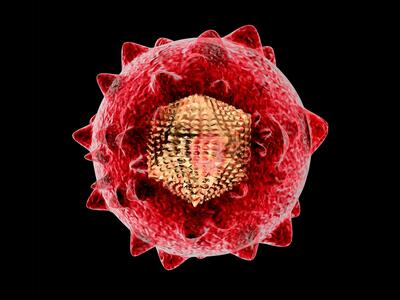

ویروس هپاتیت

راه نفوذ ویروس هپاتیت C به سلولها کشف شد

دانشمندان چگونگی نفوذ ویروس هپاتیت C به سلولها را کشف کردهاند.این یافته جدید امکان تولید واکسن برای این بیماری مرگبار